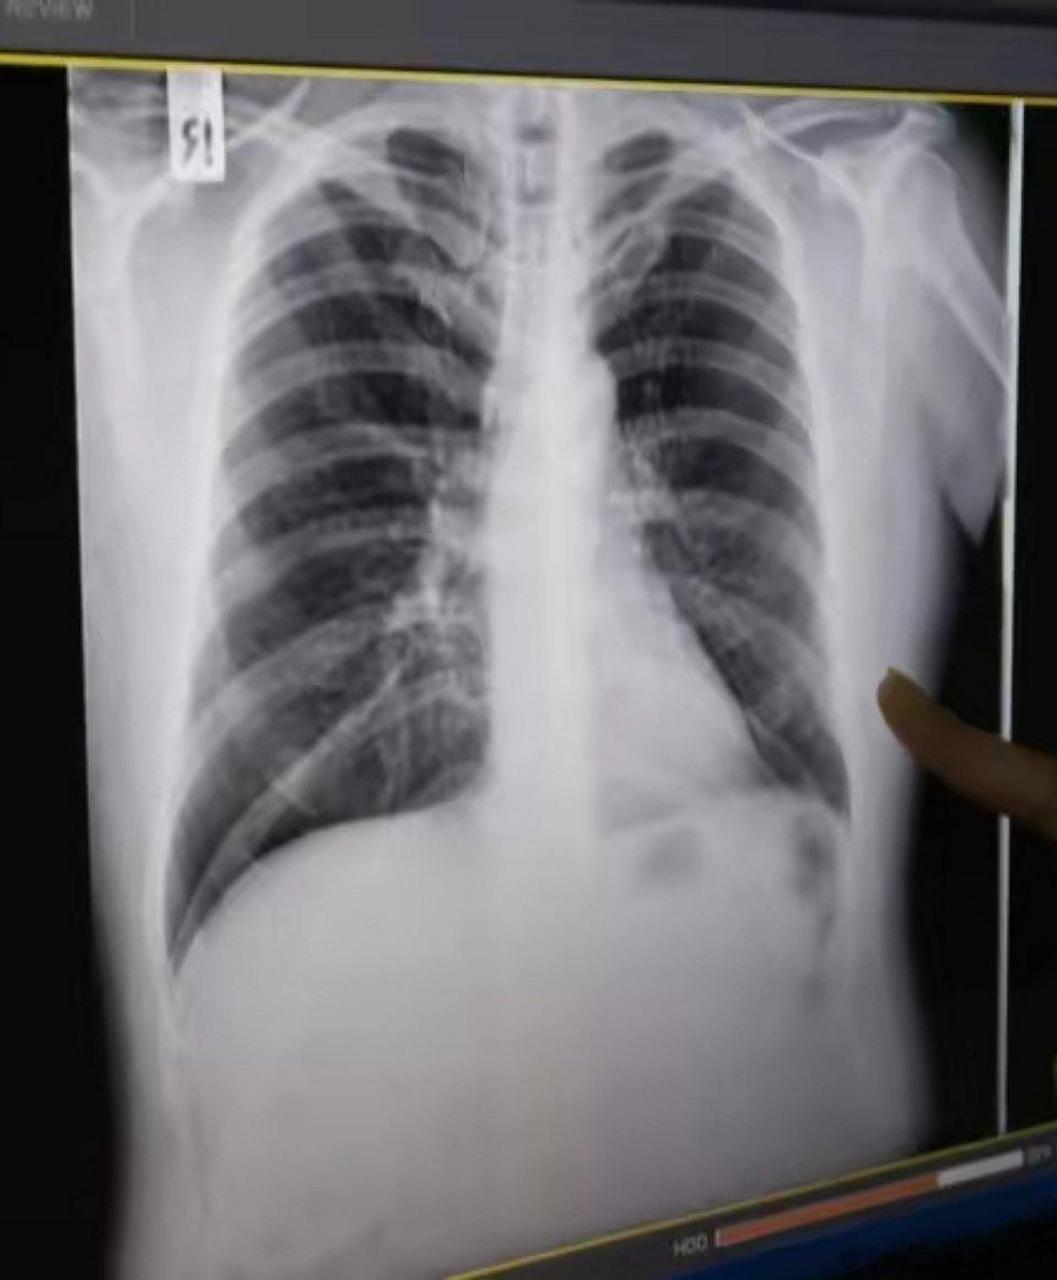

双侧多发肺大泡一例